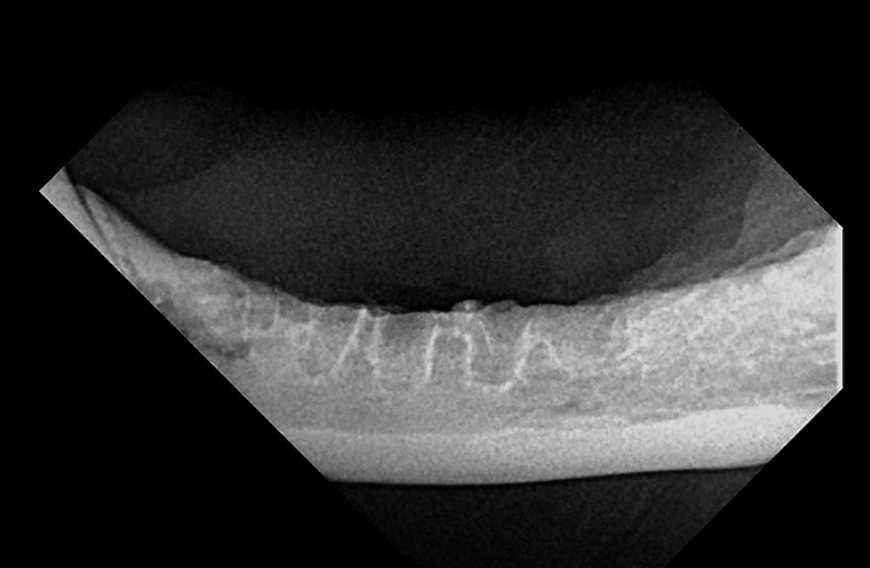

Los pacientes con mucositis caudal en el área delimitada medialmente por los pliegues palatoglosos y las fauces (antes denominada faucitis, que es menos precisa) generalmente no responderán al tratamiento de Fase I; A menudo se recomienda la intervención de fase II (es decir, extracciones de la boca caudal, extracción completa de todos los premolares y molares restantes y desbridamiento de los tejidos inflamados [p. Ej., Márgenes gingivales friables y crestas alveolares]). Los incisivos también se pueden quitar, pero, a menos que haya una inflamación significativa o pérdida ósea, los dientes caninos se conservan debido al tiempo quirúrgico adicional y al gasto requerido para las extracciones de boca completa y / o la preferencia del propietario para preservar los caninos.